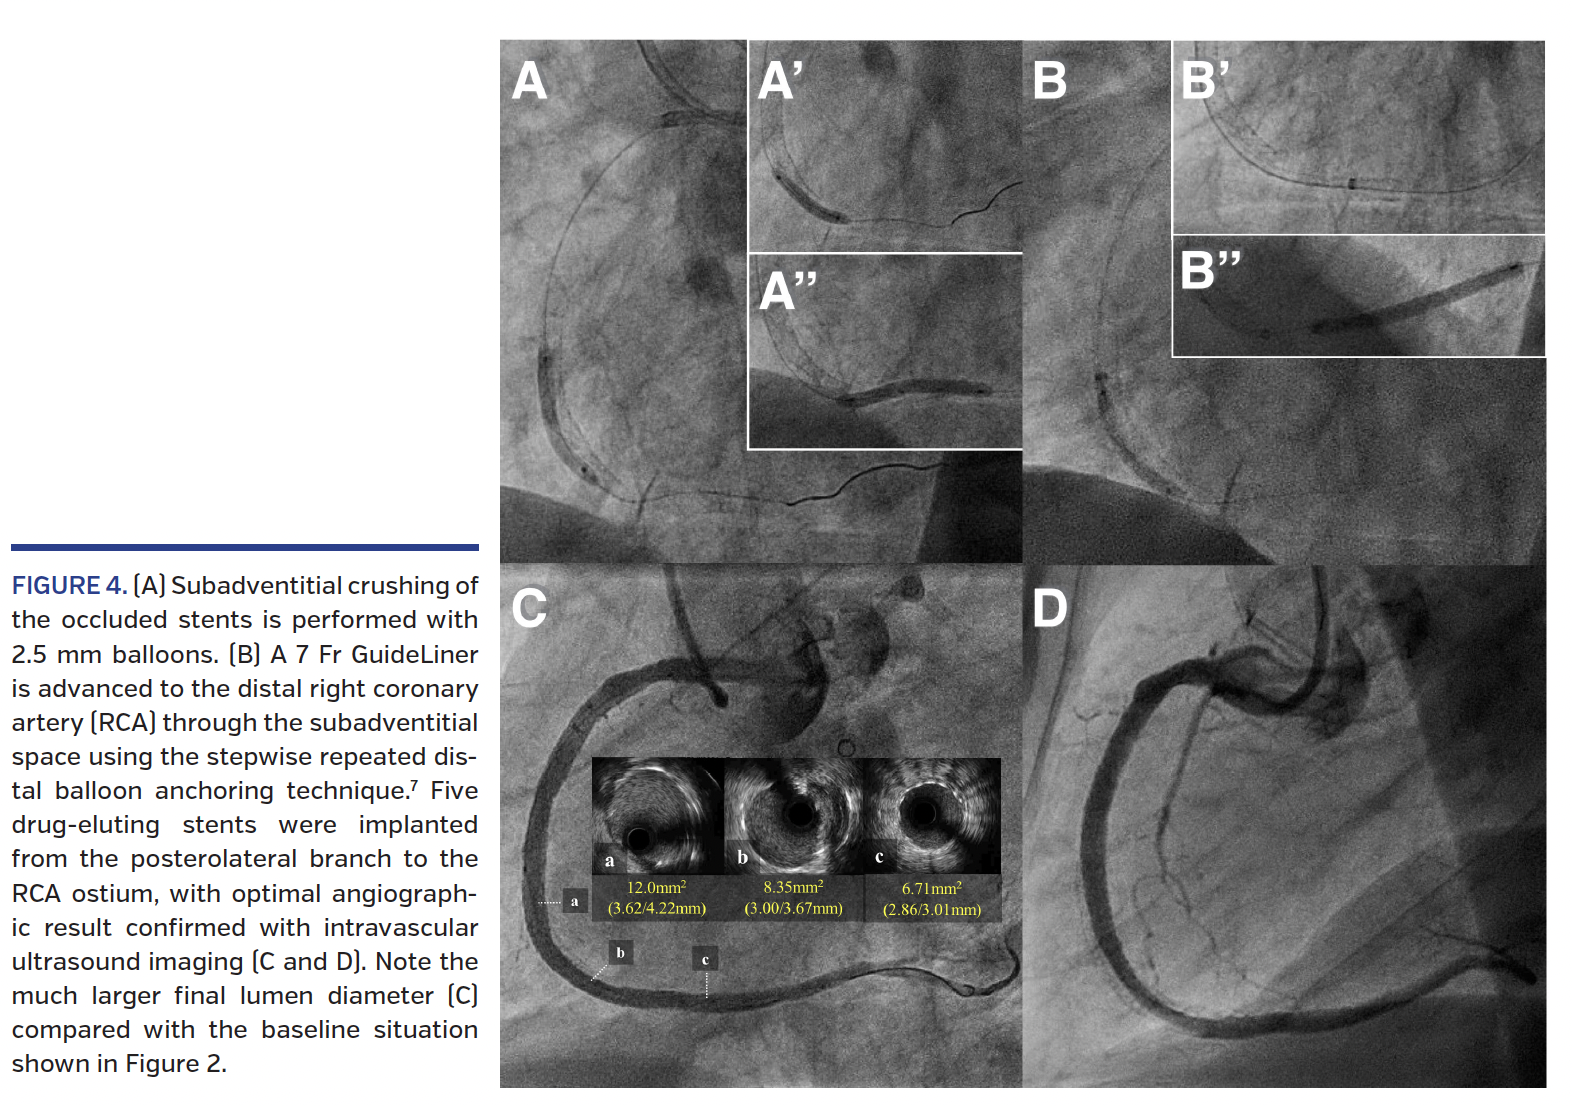

Subsequently, a knuckle wire was created with a Fielder FC (Asahi Intecc). Due to difficulty in advancing the knuckled wire through the subadventitial space in the crushed stent area, the Turnpike LP itself was knuckled and successfully advanced to the distal RCA (Figure 3E). The subintimal tracking and re-entry (STAR) technique was performed and the wire crossed into the PL branch (Figure 3F). Extensive lesion predilation was then achieved using a 2.5 x 20 mm non-compliant (NC) balloon and a 2.5 x 30 mm semicompliant balloon, with subsequent crushing of the occluded stents (Figure 4A). However, it was not possible to pass a new stent to the distal RCA through the subadventitial space. A 7 Fr GuideLiner mother-and-child catheter (Vascular Solutions) was therefore advanced through the channel created in the subadventitial space, outside the occluded/crushed stents, using the stepwise repeated distal balloon anchoring technique7 (Figure 4B; Videos 1 and 2), with subsequent implantation of five overlapping drug-eluting stents (3.0 x 38 mm, 3.5 x 38 mm, 4.0 x 38 mm, 4.0 x 38 mm, and 5.0 x 12 mm) from the PL branch to the ostial RCA. High-pressure postdilation was carried out using 3.5 mm, 4.0 mm, 4.5 mm, and 5.0 mm NC balloons from the distal to the proximal segments. Excellent angiographic result was obtained (Figures 4C and 4D), and both intravascular ultrasound (IVUS) and optical coherence tomography confirmed optimal crushing of the occluded stents and expansion of the newly implanted stents (Figure 5).

In the current case, a large-bore device – a 7 Fr GuideLiner – was advanced through a long subadventitial channel from the mid to the distal RCA. To the best of our knowledge, this is the first description of this technique. This maneuver became necessary because stent delivery to the distal vessel was impossible, despite extensive crushing of the occluded stents. Fully expanded balloons in this setting (Figure 4A) indicated that the underlying mechanism was subadventitial space recoil. Therefore, utilization of a device able to prevent collapse of the subadventitial space, such as a mother-and-child catheter, appeared the best choice. Advancing the GuideLiner with the stepwise repeated distal-balloon anchoring technique7 (Figure 4B) was crucial to the delivery of long stents to the distal vessel, thus avoiding friction and interference by the distorted struts of the long, crushed, occluded stents. This novel utilization of a mother-and-child catheter through a long subadventitial channel following external crushing of occluded stents confirms the high tensile strength of the adventitia.12